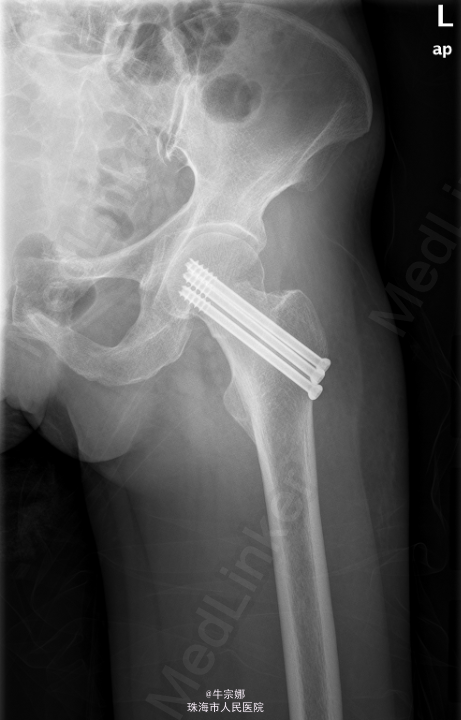

初步诊断:左股骨颈骨折.全麻下行左股骨颈骨折闭合复位内固定术. 取以左股骨粗隆下方约7cm的外侧经皮切口约3cm,C臂机引导下在左股骨粗隆下方约6cm、5cm、4cm处依次钻入3枚导针达股骨头部,见导针位置好,骨折对位对线良好,测深,分别旋入三枚空心拉力螺钉。再次透视位线良好。拔除导针,予以皮肤缝合。